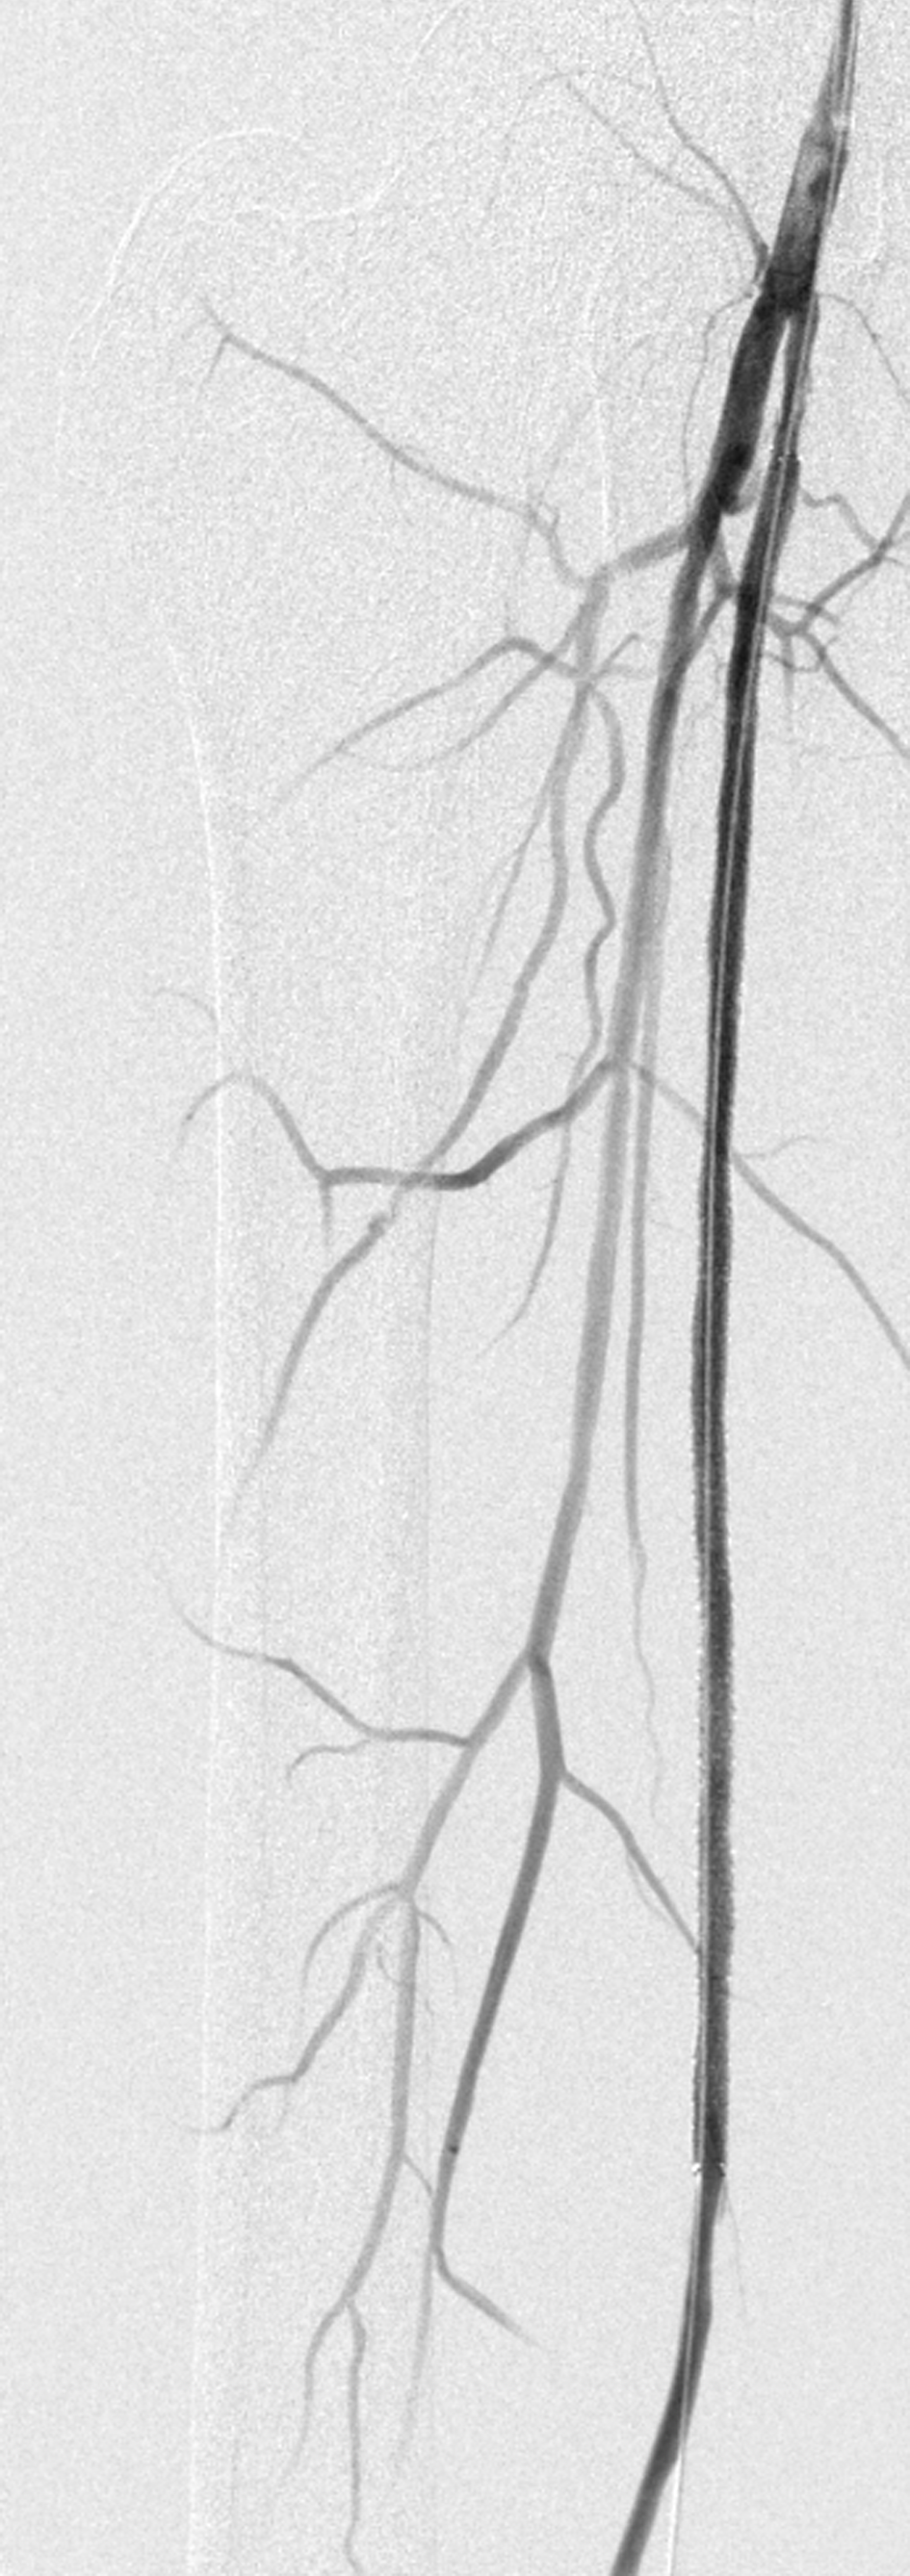

Abb. 2: Langstreckiger Verschluss der A. femoralis superficialis. Abb. 2: Langstreckiger Verschluss der A. femoralis superficialis. © Krankenberg H. Hamburger Ärzteblatt 2020; 74: 13-16 © Hamburger Ärzteverlag, Hamburg

Besonders häufig finden sich atherosklerotische Veränderungen in der A. femoralis superficialis, die ebenfalls einem erheblichen Bewegungsstress ausgesetzt ist. Läsionen in diesem Gefäß sollten bis zu einer Länge von 25 cm zunächst endovaskulär angegangen werden. Mit einer medikamentenbeschichteten Ballon-Angioplastie bleibt die Arterie länger offen als mit dem Standardballon (70 % vs. 45 %). Bei Residualstenosen oder fluss-limitierender Dissektion können zusätzliche Stents eingesetzt werden. Spot-Stenting kombiniert mit medikamentenbeschichteten Ballons hat sich bei längeren Läsionen bewährt. Patienten mit schwerer Kalzifikation profitieren von einer primären Stentimplantation. Direkte Vergleichsstudien Ballon vs. Stent fehlen allerdings bislang.